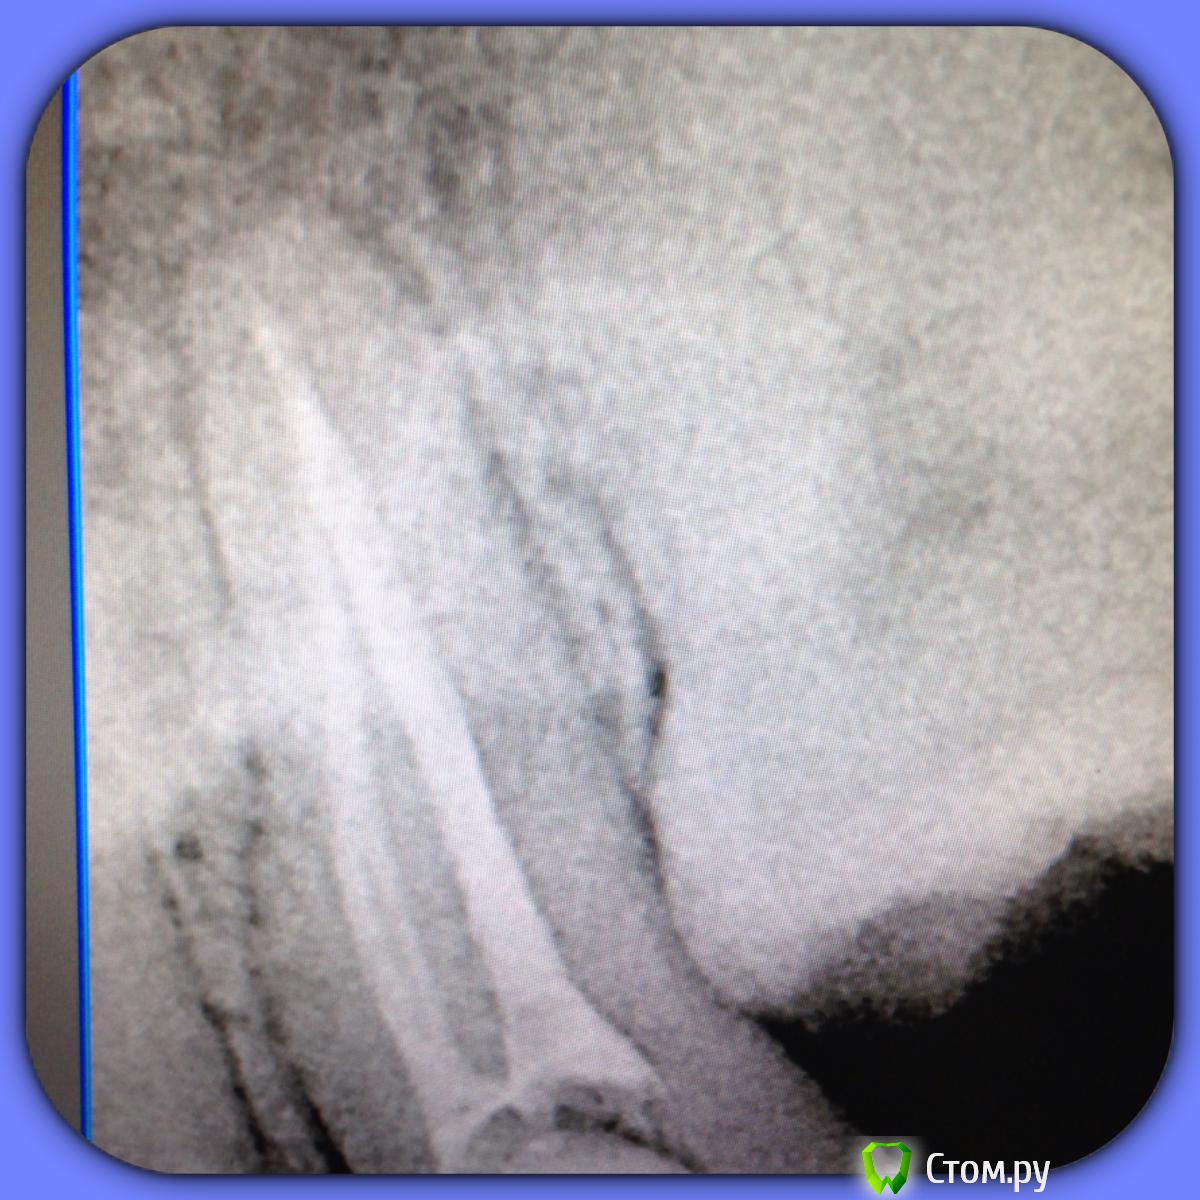

SSTi Опубликовано 25 августа, 2014 Автор Поделиться Опубликовано 25 августа, 2014 Найдите фэйл))) 37 Ссылка на комментарий

M@estro Опубликовано 25 августа, 2014 Поделиться Опубликовано 25 августа, 2014 В мя грохнул Ссылка на комментарий

SSTi Опубликовано 25 августа, 2014 Автор Поделиться Опубликовано 25 августа, 2014 В мя грохнул Неа) ничего не сломал. Медиальные сходятся за 2 мм до апекса) Ссылка на комментарий

SSTi Опубликовано 25 августа, 2014 Автор Поделиться Опубликовано 25 августа, 2014 (изменено) Ладно. Ответ - выход мш в дистальном на 1мм от упора. А все дело в том, что сформировал стопупор 40.02. Открываю свой чудо ящик, ищу гутту 40.02 , ищу , ищу , ищу... А она кончилась. Ассорти от 45 и выше кончились. Пришлось брать 35.02. ... Только моя дурная голова потом додумалась, что надо было просто обрезать чуть штифт и все. Хвост отпаянный измерил - короче на 1 мм , чем должен был быть. Одно душу греет - мылись мы как никогда. Изменено 25 августа, 2014 пользователем SSTi 1 Ссылка на комментарий